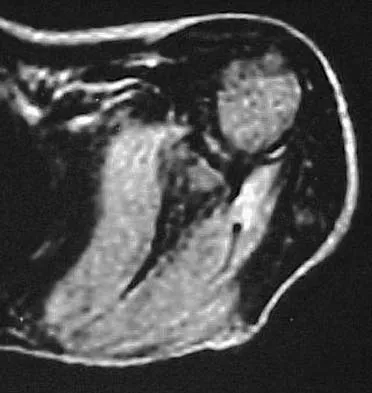

A 43-year-old man has had right groin pain for the past 3 months. A radiograph, CT scan, and biopsy specimen are shown in Figures 18a through 18c. What is the most likely diagnosis?

Explanation

A 77-year-old man has had increasing right knee pain for the past 3 months. A radiograph and coronal T1-weighted MRI scan are shown in Figures 19a and 19b. A biopsy specimen is shown in Figure 19c. What is the most likely diagnosis?

Explanation